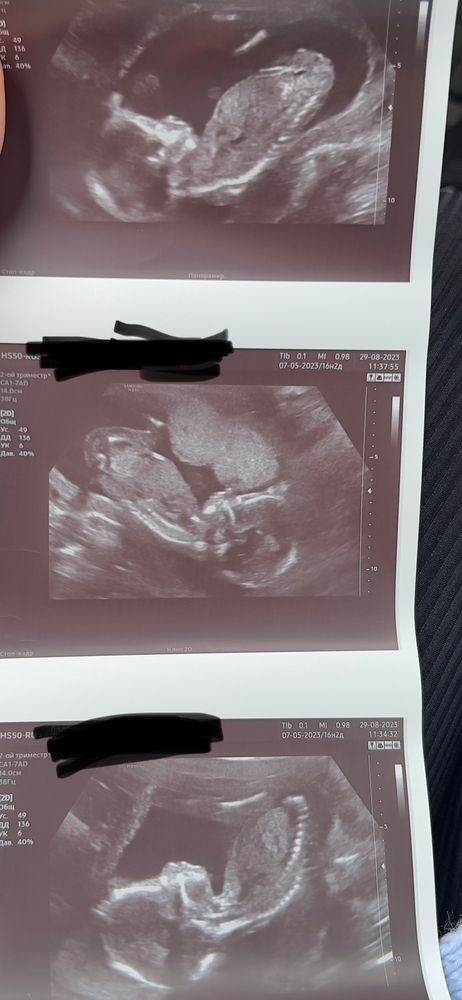

жду девочку, 18 неделя Рыбинск

Определение Пола ?

Полового бугорка вообще не видно, но по строению черепа предположу, что мальчишка :)